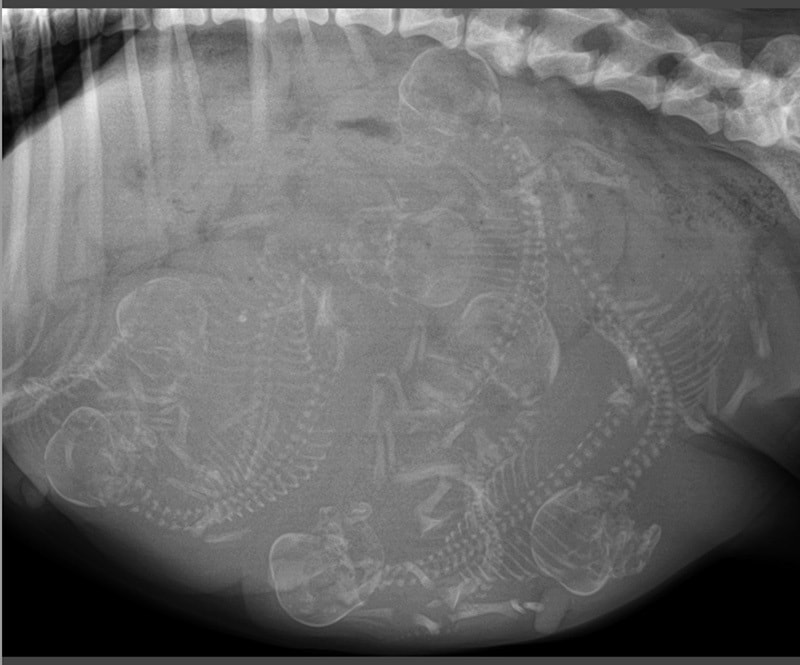

Where Breeders and Veterinarians Join Forces to Create Future Generations of Well-Bred Dogs

Our goal is to be your partner for success with your kennel and breeding program. Our highly trained staff understands the commitment you have made to your breed. We are here to help you produce healthy, sought after puppies. Whether you are producing Best in Show conformation dogs, Performance dogs, or family pets, we strive to keep your whelping boxes full of healthy puppies and happy dams, and your stud dogs thriving and preserved for the future.